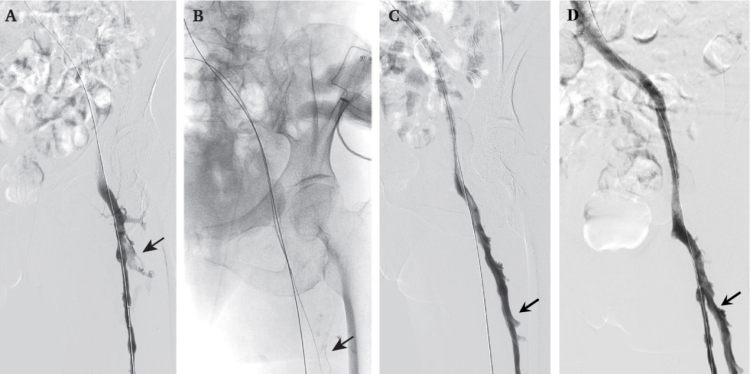

在既往下肢深静脉血栓的介入治疗中,临床只针对顺行静脉造影可见的腘静脉、股浅静脉、股总静脉和髂静脉进行血栓清除,对于顺行造影无法显影的股深静脉,其血栓常被忽视。这种治疗方式导致血栓清除不彻底、残余血栓复发率高,严重制约了介入治疗的长期效果。

仁济医院血管外科张岚团队深耕深静脉血栓介入治疗领域10余年,在原有介入治疗基础上,创新性通过逆向方式寻找到股深静脉,对既往被忽视的股深静脉血栓进行彻底清除,从而使血栓的远期并发症率从28%下降至10%,大幅度提高了介入治疗的长期疗效。